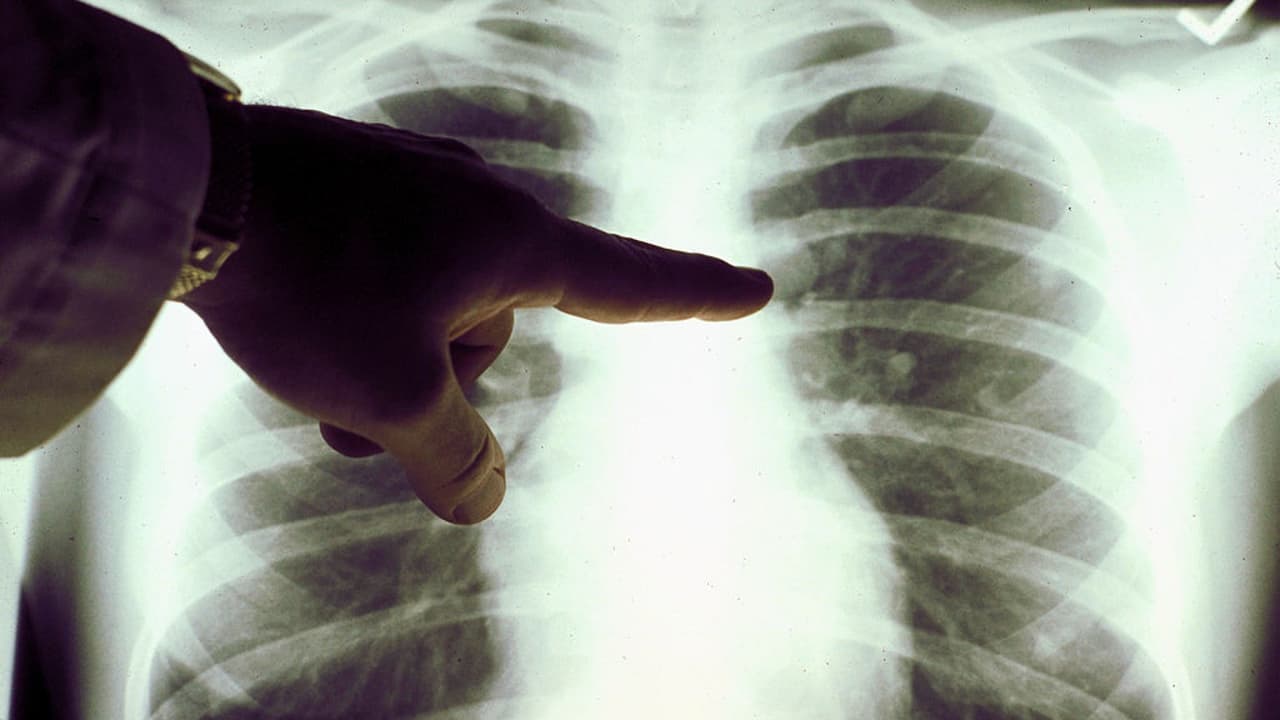

Recomendaciones de un médico experto para evitar y tratar enfermedades pulmonares

El Dr. Harry Karmouty Quintana explica que este tipo de padecimientos se han convertido en la tercera causa de muerte en EEUU. Para evitarlos recomienda proteger las vías respiratorias permanentemente y en especial en lugares donde pueda haber mucho polvo u otro tipo de partículas.